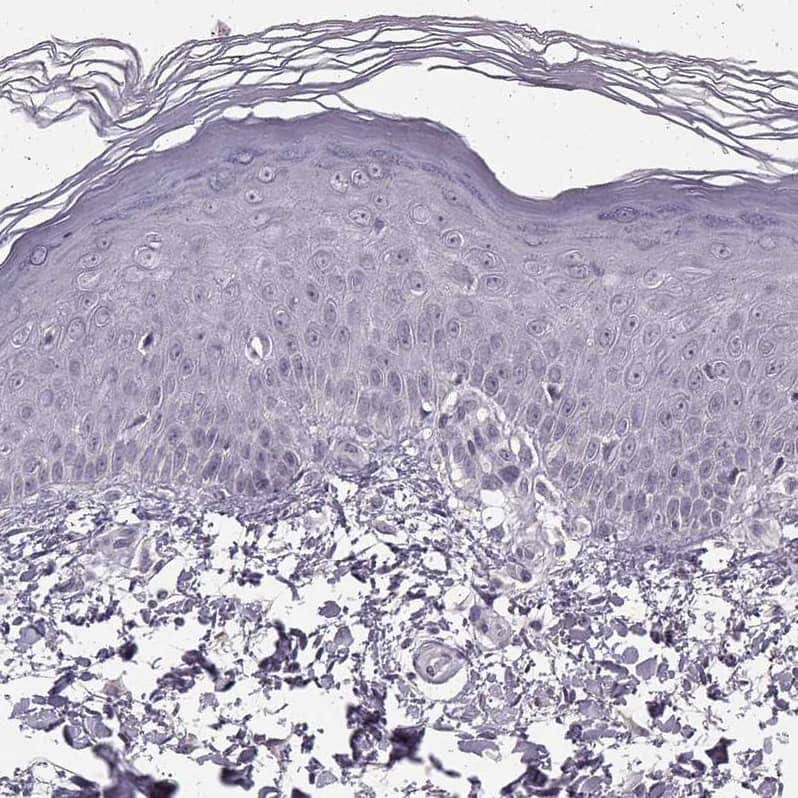

Orthogonal Strategies: Analysis in human heart muscle and skin tissues using NBP3-44495 antibody. Corresponding N-Cadherin RNA-seq data are presented for the same tissues.

Staining of human skin shows no positivity in epidermal cells as expected.